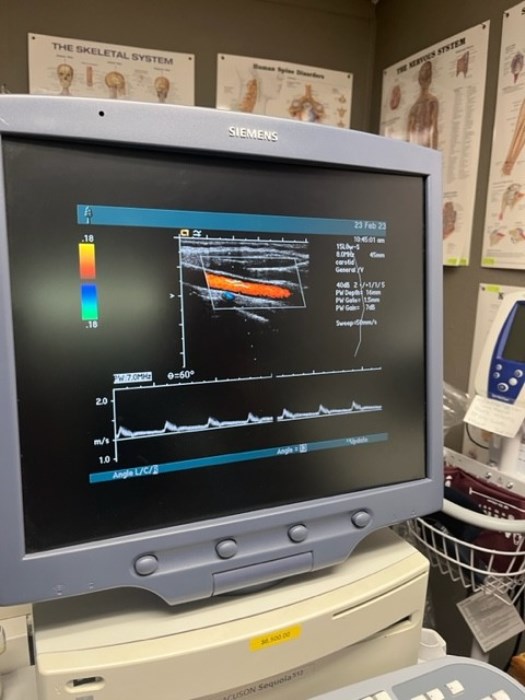

Siemens Sequioa Ultrasound

Pre-owned. In good working condition. Shown as is. Siemens Sequoia Ultrasound. DOM: 2006

Probes: 15L8w, 4V1, 10V4, 6L3, 4C1